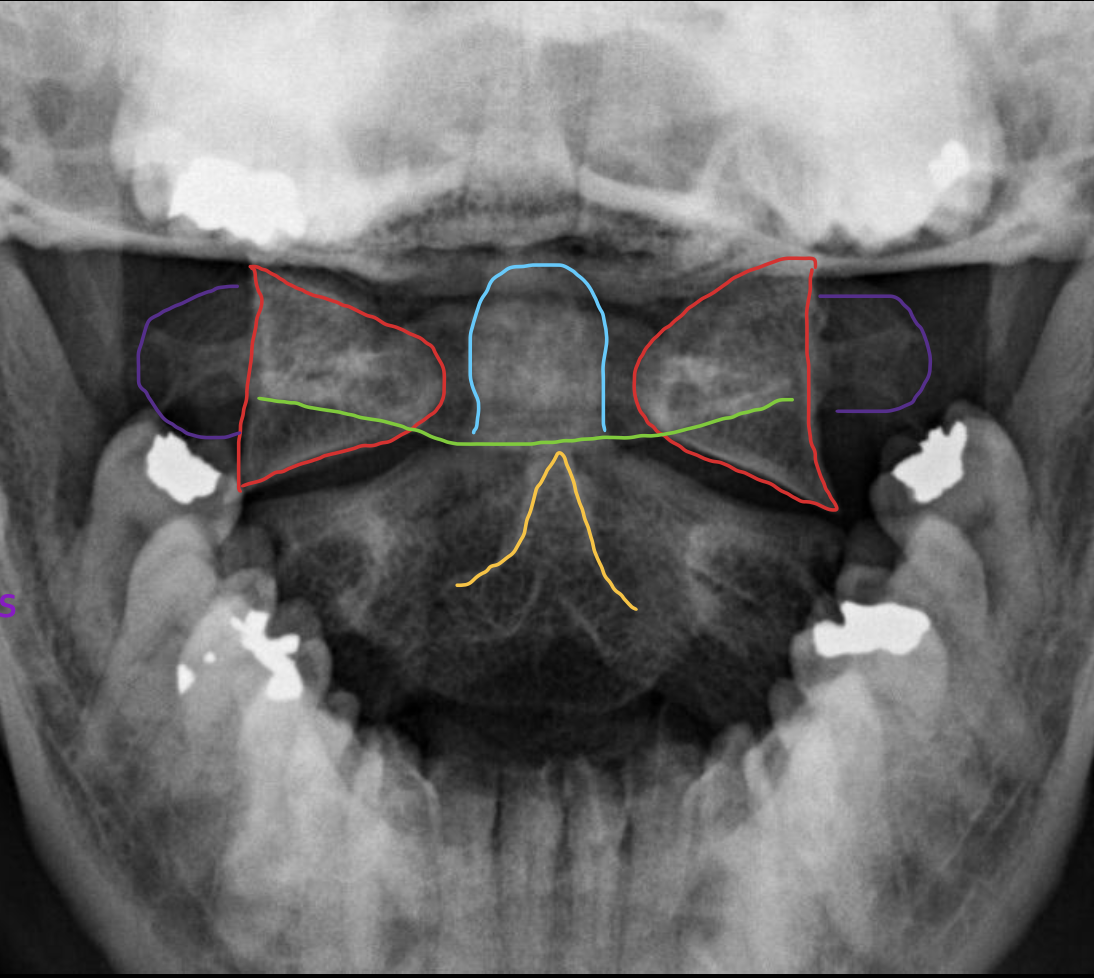

寰椎侧块

C1 lateral mass

枢椎棘突

C2 spinous process

寰椎后弓

Posterior arch C1

寰椎横突

C1 transverse process